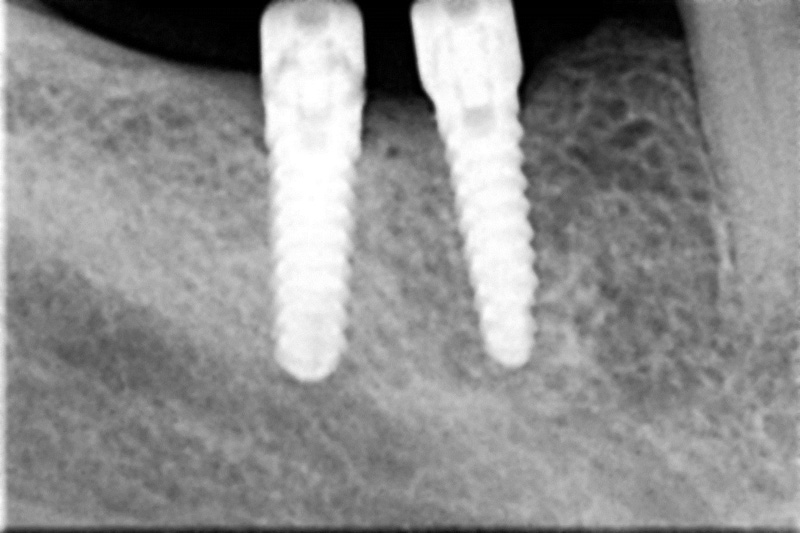

Protetické řešení může být pomocí můstku, který je kotvený na implantátech nebo pomocí jednotlivých korunek na implantátech.

V zásadě je možné do těchto můstků zařadit i přirozené zuby, zejména pokud je potřeba tyto zuby ošetřit proteticky

- korunkami. Korunky nebo můstky mohou být na implantáty nacementovány nebo přišroubovány.